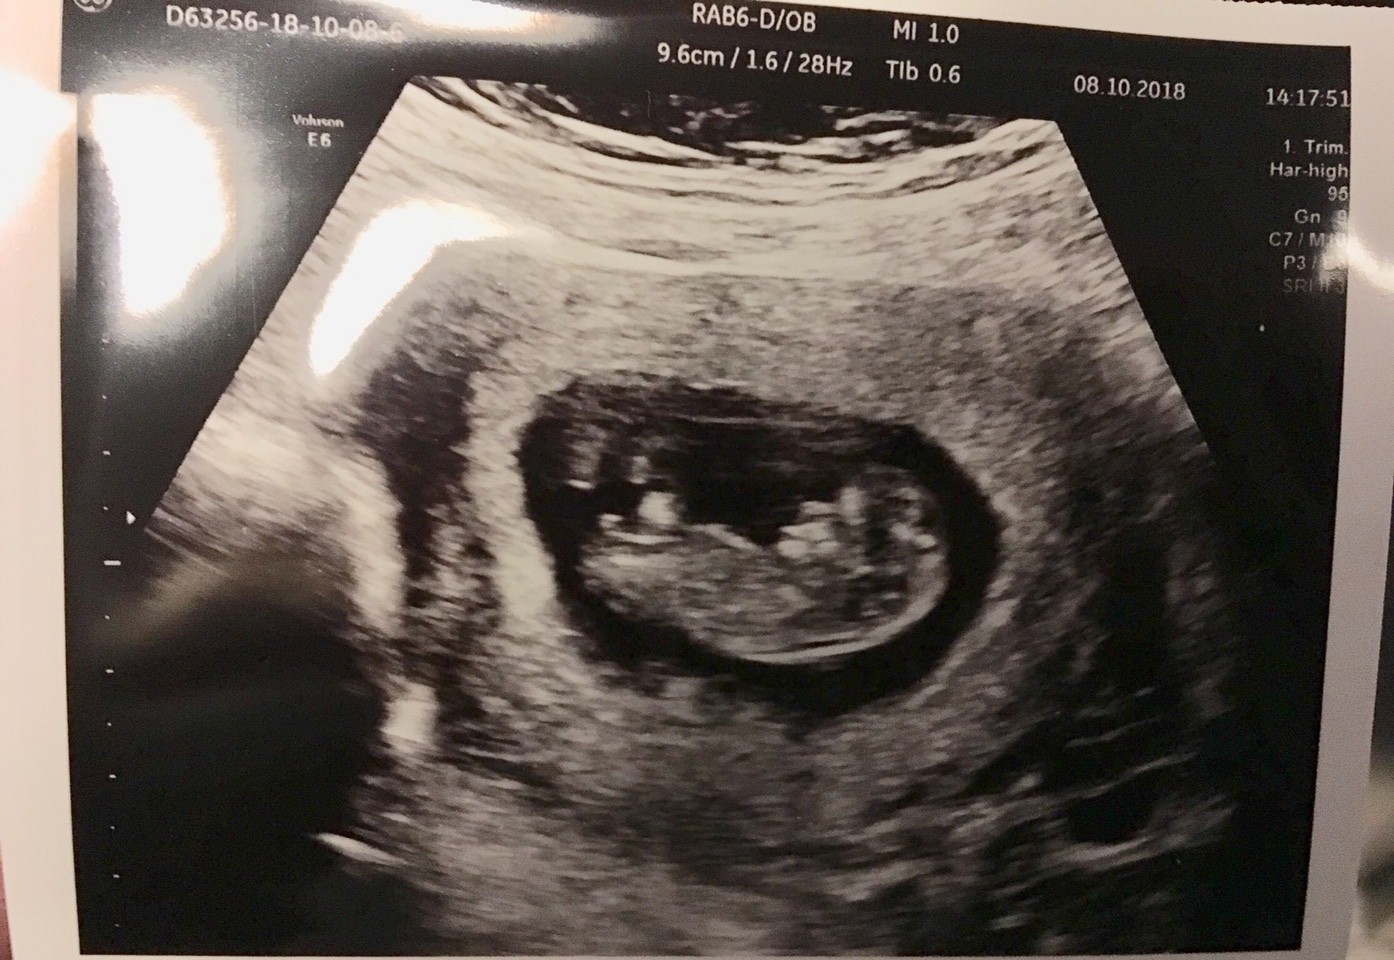

Jestem po wizycie. Z dzidzia wszystko w porzadku, pieknie rosnie, ma nozki, raczki, pieknie widac mózg, na genetyczne jeszcze za wcześnie, podpytywałam ją czy widzi jakies nieprawidłowości, powiedziała, że na razie wszystko jest w normie, nt ale to trzeba sprawdzic miedzy 12-14tc, pieknie tez bylo widac kręgosłup. No i tak po cichu powiedziala, ze ona tu chyba chlopaka widzi[emoji4] ale dzidzia jest tak mala, ze moze sie mylic.

Nastepna wizyta bedzie u mojego w pl i tam zrobie badania genetyczne, bo sie nalozylo z naszym urlopem, ale moze to dobrze [emoji4]

W ogole ta gin jest przesymatyczna [emoji4]

Aha. Z tych mniej przyjemnych rzeczy. Mam znowu poczatek infekcji. Mowilam jej ze w pierwszej ciazy tez ciagle cos mialam, a po przed i po zupelnie nic, powiedziala, ze widocznie organizm nie radzi sobie przy kontakcie z inna flora bakteryjna i seks w prezerwatywie nam zostaje. Dostalam leki znowu [emoji53]

I tu moj chyba Mikolaj ssajacy paluszka [emoji173]️